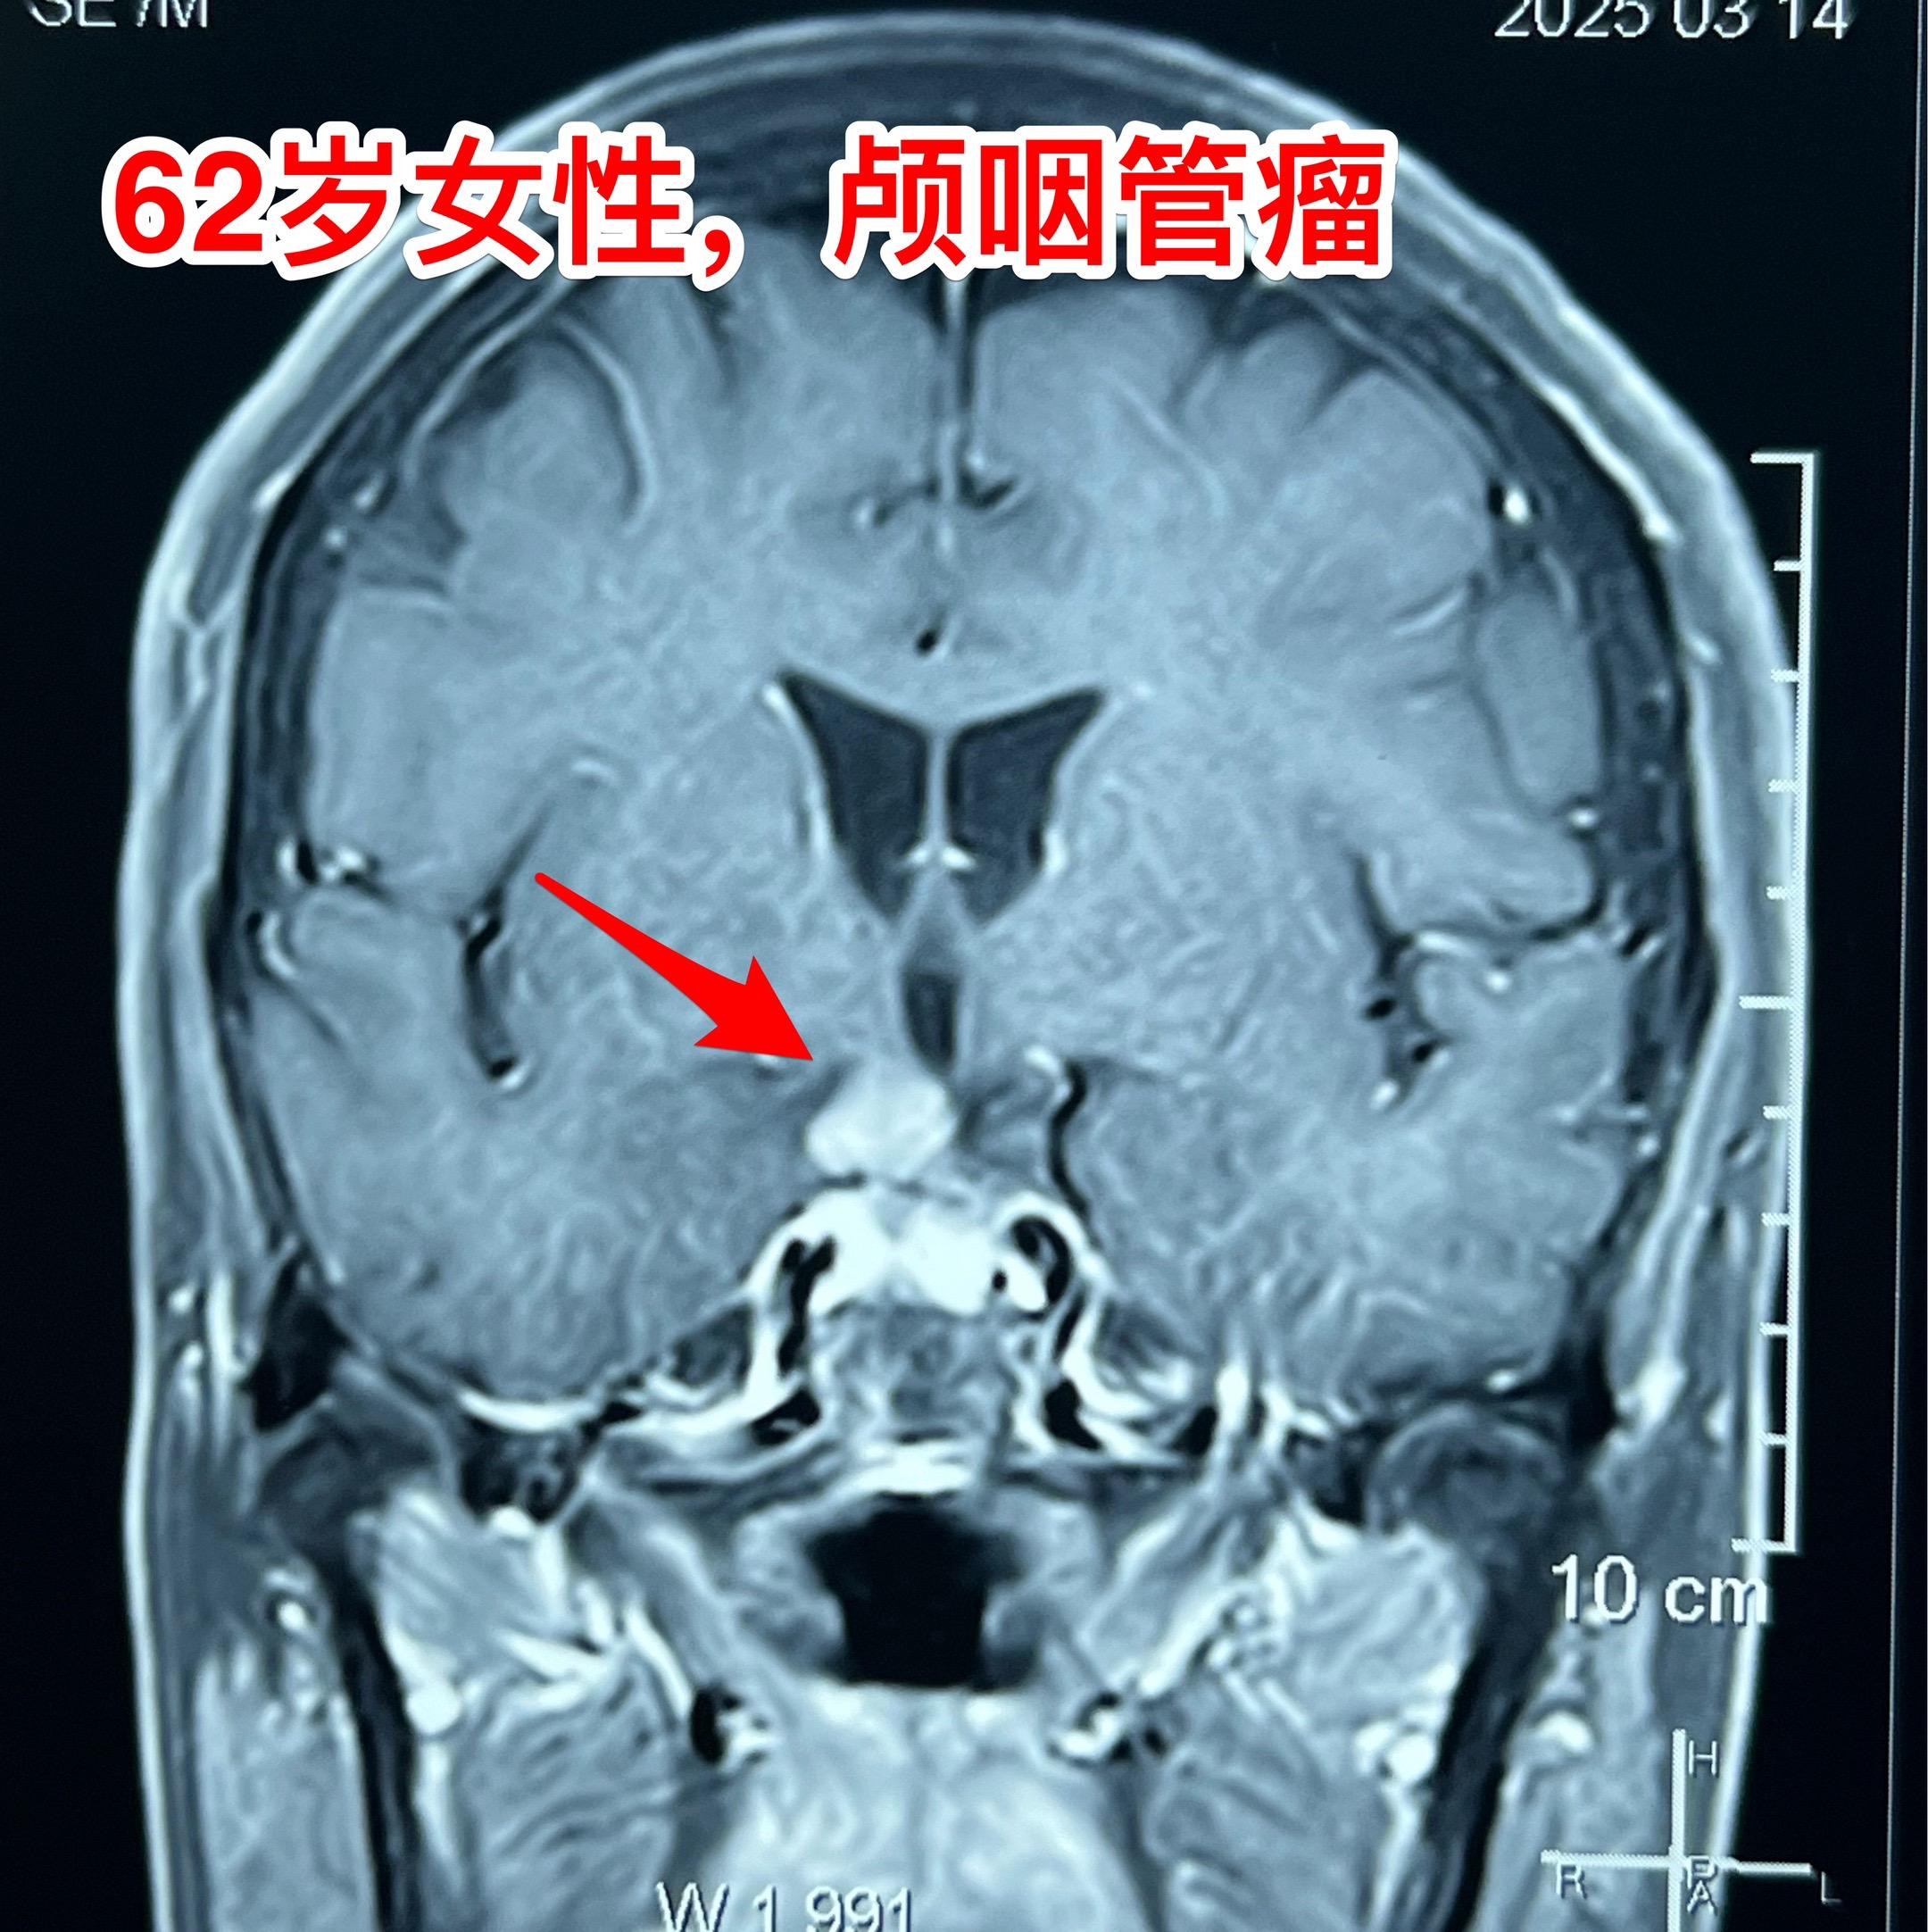

经翼点入路切除颅咽管瘤-不能忘记的入路 经翼点入路切除颅咽管瘤,曾经是广泛使用的一种入路,当然有其优点。近十几年使用这个入路切除颅咽管瘤的机会大大减少了。 对于比较小的鞍上型颅咽管瘤或者自中线偏向侧裂池方向生长的颅咽管瘤,这个入路是很适合的。 3月21日为62岁女性病人切除颅咽管瘤,采用的就是经翼点入路。肿瘤得到完全切除,垂体柄得到保护[强]